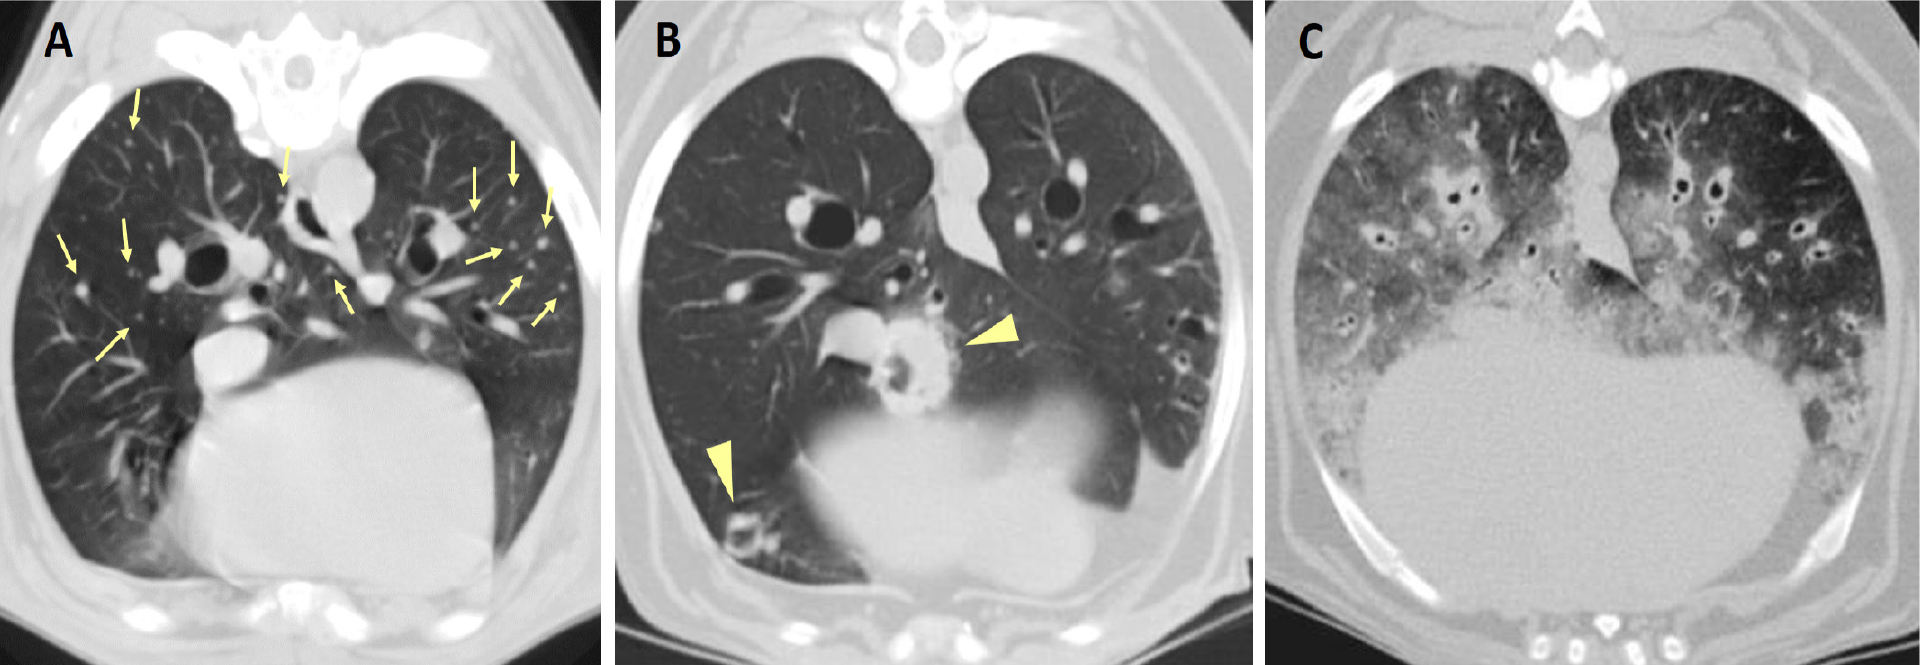

Als Masse werden per definitionem Läsionen von mehr als drei Zentimetern bezeichnet (Abb. 1). Auch kleine Herde mit Durchmessern von ein bis zwei Millimetern sind auf CT-Bildern meist gut erkennbar (Abb. 2).

Gelegentlich weisen Lungentumoren Mineralisationen auf, häufiger betrifft das Tumoren bei Katzen. Bei großen Massen sind häufig in den zentralen Bereichen Gas- und Flüssigkeitseinlagerungen nachweisbar (Marolf et al., 2011, Schwarz und Johnson, 2011, Aarsvold et al., 2015). Größe, Zahl und Verteilung der Rundherde variieren sehr und erlauben kaum eine Einordnung der identifizierten Strukturen als Primärtumor oder Metastase sowie die Abgrenzung von nicht tumorösen Veränderungen. Neben Rundherden und Massen können sich pulmonale Tumoren in selteneren Fällen auch als sogenannte Parenchymveränderungen präsentieren. Dabei handelt es sich um flächige Veränderungen mit alveolärem, broncho-interstitiellem oder gemischtem Strukturmuster (Marolf et al., 2011, Abb. 2).

• Kavernenbildung infolge zentraler Nekrosen bei großen Läsionen (Abb. 2B) (Parry et al., 2021)

• Pleurale Massen, Liquidothorax bzw. Pneumothorax durch Invasion oder Metastasierung in den Pleuraraum (Marolf et al., 2011, Aarsvold et al., 2015)